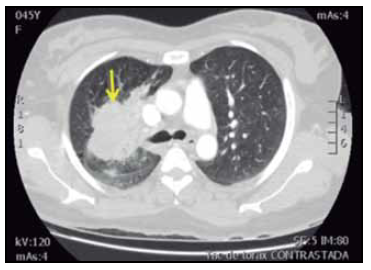

Ante los hallazgos identificados en las imágenes previas, se hicieron estudios de extensión para identificar foco neoplásico primario, la TAC contrastada de abdomen no mostró lesiones sugestivas de primario y la TAC contrastada de tórax (Figura 2) evidenció una masa pulmonar espiculada sin cavitación en el lóbulo superior derecho, adenopatías de localización hiliar derecha de 15 mm de diámetro en el eje corto y paratraqueales derechas de 13 mm de diámetro en el eje corto, sin lesiones líticas o blásticas en las estructuras óseas. La lesión pulmonar era sugestiva de carcinoma broncogénico siendo necesaria su confirmación histológica por biopsia mediante fibrobroncoscopia. Los hallazgos de la biopsia confirmaron el diagnóstico de un carcinoma de célula no pequeña compatible morfológicamente con un adenocarcinoma broncogénico (Figura 3), los marcadores de inmunohistoquímica fueron positivo para TTF1 (Figura 4) y negativo para P63 (Figura 5).

Figura 2 TAC contrastada de tórax corte axial. Se observa masa de contornos espiculados (flecha), con densidad de tejidos blandos localizada en el lóbulo superior derecho comprometiendo el bronquio para el lóbulo superior, con unas dimensiones de 67 x 57 x 57 mm, sin evidencia de cavitación central.